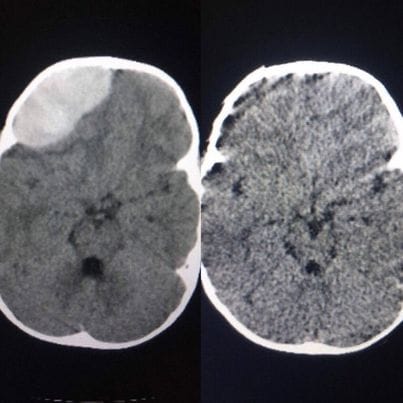

Sau khi bị ngã từ trên giường xuống nền nhà, bé H.L.Đ ở Thái Nguyên có biểu hiện nôn nhiều, chậm chạp. Gia đình bé cho biết cú ngã của bé khôngmạnh, tuy nhiên lại có biểu hiện như trên làm gia đình lo lắng và đưa tới bệnh viện A, Thái Nguyên để kiểm tra. Tại đây, sau khi thực hiện các xét nghiệm cận lâm sàng, bé được phát hiện khối máu tụ lớn ngoài màng cứng vùng trán phải, đè ép màng cứng và nhu mô não thuỳ trán phải. Các bác sĩ đã tiến hành phẫu thuật lấy khổi máu tụ. Hiện sức khoẻ bé đã bình phục.

Giải thích về vấn đề này, các bác sĩ cho rằng va chạm đó có thể làm đứt một tĩnh mạch bắc cầu, khiến máu chảy rỉ rả và đến một lúc nào đó, khi lượng máu tích tụ đủ để chèn ép lên não, sẽ gây ra các triệu chứng đau đầu, nôn ói, mắt mờ, tay chân yếu, rối loạn tri giác rồi hôn mê.

Do vậy, có nhiều trường hợp hai ba tháng sau chấn thương mới xuất hiện các triệu chứng trên, khi đó được xem là tụ máu dưới màng cứng mãn tính.

BS. Trọng cũng lưu ý dù dạng nào cũng nguy hiểm và cần được xử lý kịp thời, nếu không phát hiện sớm có thể dẫn đến tình trạng bệnh nhân có thể sống thực vật hoặc tử vong. Còn nếu được xử lý kịp thời, mổ giải áp não sớm, dẫn lưu máu tụ ra ngoài thì hầu hết phục hồi hoàn toàn ngay sau khi lấy hết máu tụ.